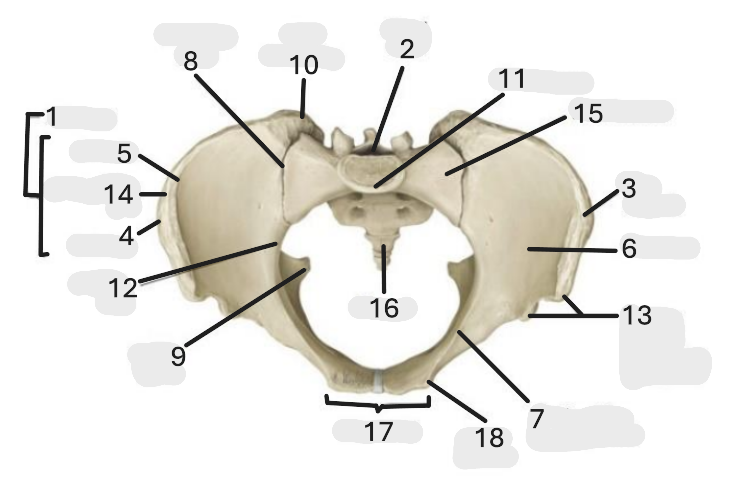

Where is the pelvic inlet

1

Where is the sacro-iliac joint

2

Where is the pubic tubercle

3

Where are the S1 body

4

Where is the ischial spine

5

Where is the ala of sacrum

6

Where is the anterior superior iliac spine

7

Where is the ischiopubic ramus

8

Where is the coccyx

9

Where is the obturator foramen

10

Where is the pubic symphysis

11

Where is the ischial tuberosity

12